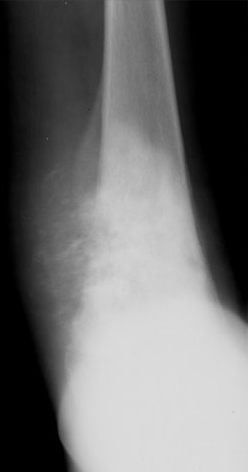

A 15 year old male comes to see you complaining of knee pain that has gone on for a few weeks after his hiking trip. His x-ray is shown below. How would you treat this kid?

He most likely has an osteosarcoma, which is the second most common malignant tumor in kids after rhabdomyosarcoma. Note Codmans triangle at the matphysis of the femur, indicating aggressive tumor growth through the bone cortex. I would treat the cancer aggressively as it could metastasize to the lungs.